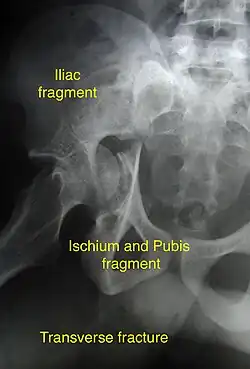

Transverse fracture showing upper iliac fragment, lower ischial and pubic fragment

Transverse fracture showing upper iliac fragment, lower ischial and pubic fragment -

Transverse fracture fixed with screws and plate

Transverse fracture fixed with screws and plate

| Transverse | In this variety of fracture, the innominate bone is broken such that the upper part consists of ilium with weight bearing dome and the lower part consists of ischium and pubic bones. It typically occurs when the injuring force is applied from the side, against the greater trochanter of the femur bone, as in a fall on the side or being hit on the side. This is a two part fracture, but though both columns are broken, it is not a true both-column fracture, as the weight bearing dome is still attached to main ilium.

In this variety of fracture, the innominate bone is broken such that the upper part consists of ilium with weight bearing dome and the lower part consists of ischium and pubic bones. It typically occurs when the injuring force is applied from the side, against the greater trochanter of the femur bone, as in a fall on the side or being hit on the side. This is a two part fracture, but though both columns are broken, it is not a true both-column fracture, as the weight bearing dome is still attached to main ilium. Depending on the level at which the fracture line passes in relation to weight bearing area, the transverse fracture is further subdivided into types:

X-ray visualization is best done in Antero posterior view and Iliac and obturator oblique views. In CT scan the characteristic feature is that the fracture line runs from front to back. CT scan also helps in identifying impaction of bone pieces and if there are pieces in the joint |